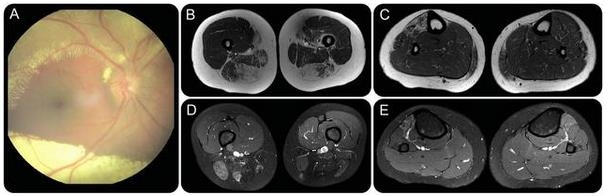

患者既往曾诊断为轻度症状性 Coats 病(CD,见图示)。肌肉 MRI 高度提示患者为 1 型面肩肱型肌营养不良(FSHD1,见图示)。基因检测证实了这一诊断。

图(A)眼底镜检查显示视网膜萎缩,视网膜周围大量渗出。肌肉 MRI 轴位像显示大腿后部肌肉和右侧胫前肌肉被脂肪组织所替代。B、C 为 T1 像,D、E 为 T2 压脂像

FSHQ1 是一种常染色体显性遗传性肌肉萎缩性疾病,但也会伴有除肌肉系统以外的表现,包括感音神经性耳聋,伴有毛细血管扩张的复杂性视网膜血管病变,比如 CD。在伴有视网膜脱落、视网膜微血管瘤形成和视网膜毛细血管形成风险的患者中,CD 可能是其特征之一。